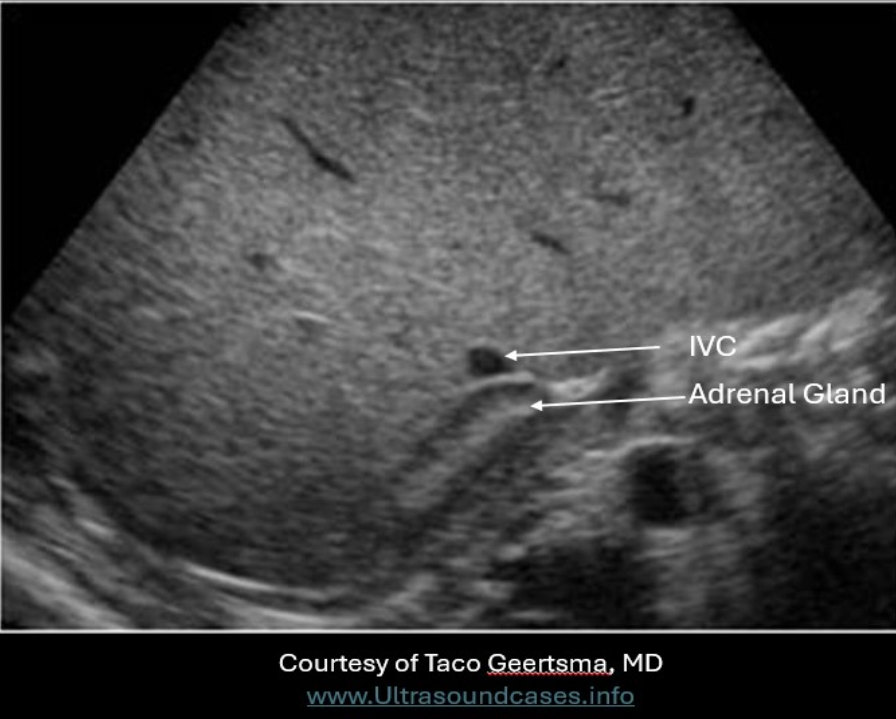

Which of the following is true regarding the anatomic position of the right adrenal gland?

A. posterior to the IVC

Right Adrenal Gland - medial to right lobe of liver; posterior to IVC; superomedial to the kidney; lateral to the right crura